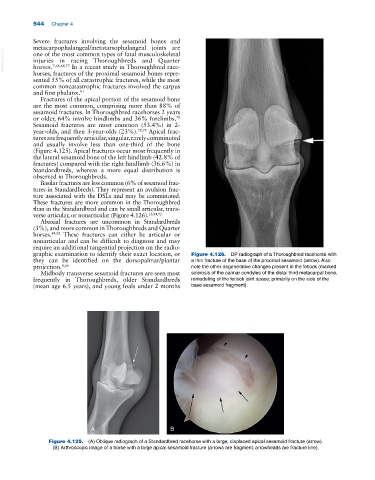

graphic examination to identify their exact location, or Figure 4.126. DP radiograph of a Thoroughbred racehorse with

they can be identified on the dorsopalmar/plantar a thin fracture of the base of the proximal sesamoid (arrow). Also

projection. 8,66 note the other degenerative changes present in the fetlock (marked

Midbody transverse sesamoid fractures are seen most sclerosis of the palmar condyles of the distal third metacarpal bone,

frequently in Thoroughbreds, older Standardbreds remodeling of the fetlock joint space; primarily on the side of the

(mean age 6.5 years), and young foals under 2 months base sesamoid fragment).

Figure 4.125. (A) Oblique radiograph of a Standardbred racehorse with a large, displaced apical sesamoid fracture (arrow).

(B) Arthroscopic image of a horse with a large apical sesamoid fracture (arrows are fragment; arrowheads are fracture line).